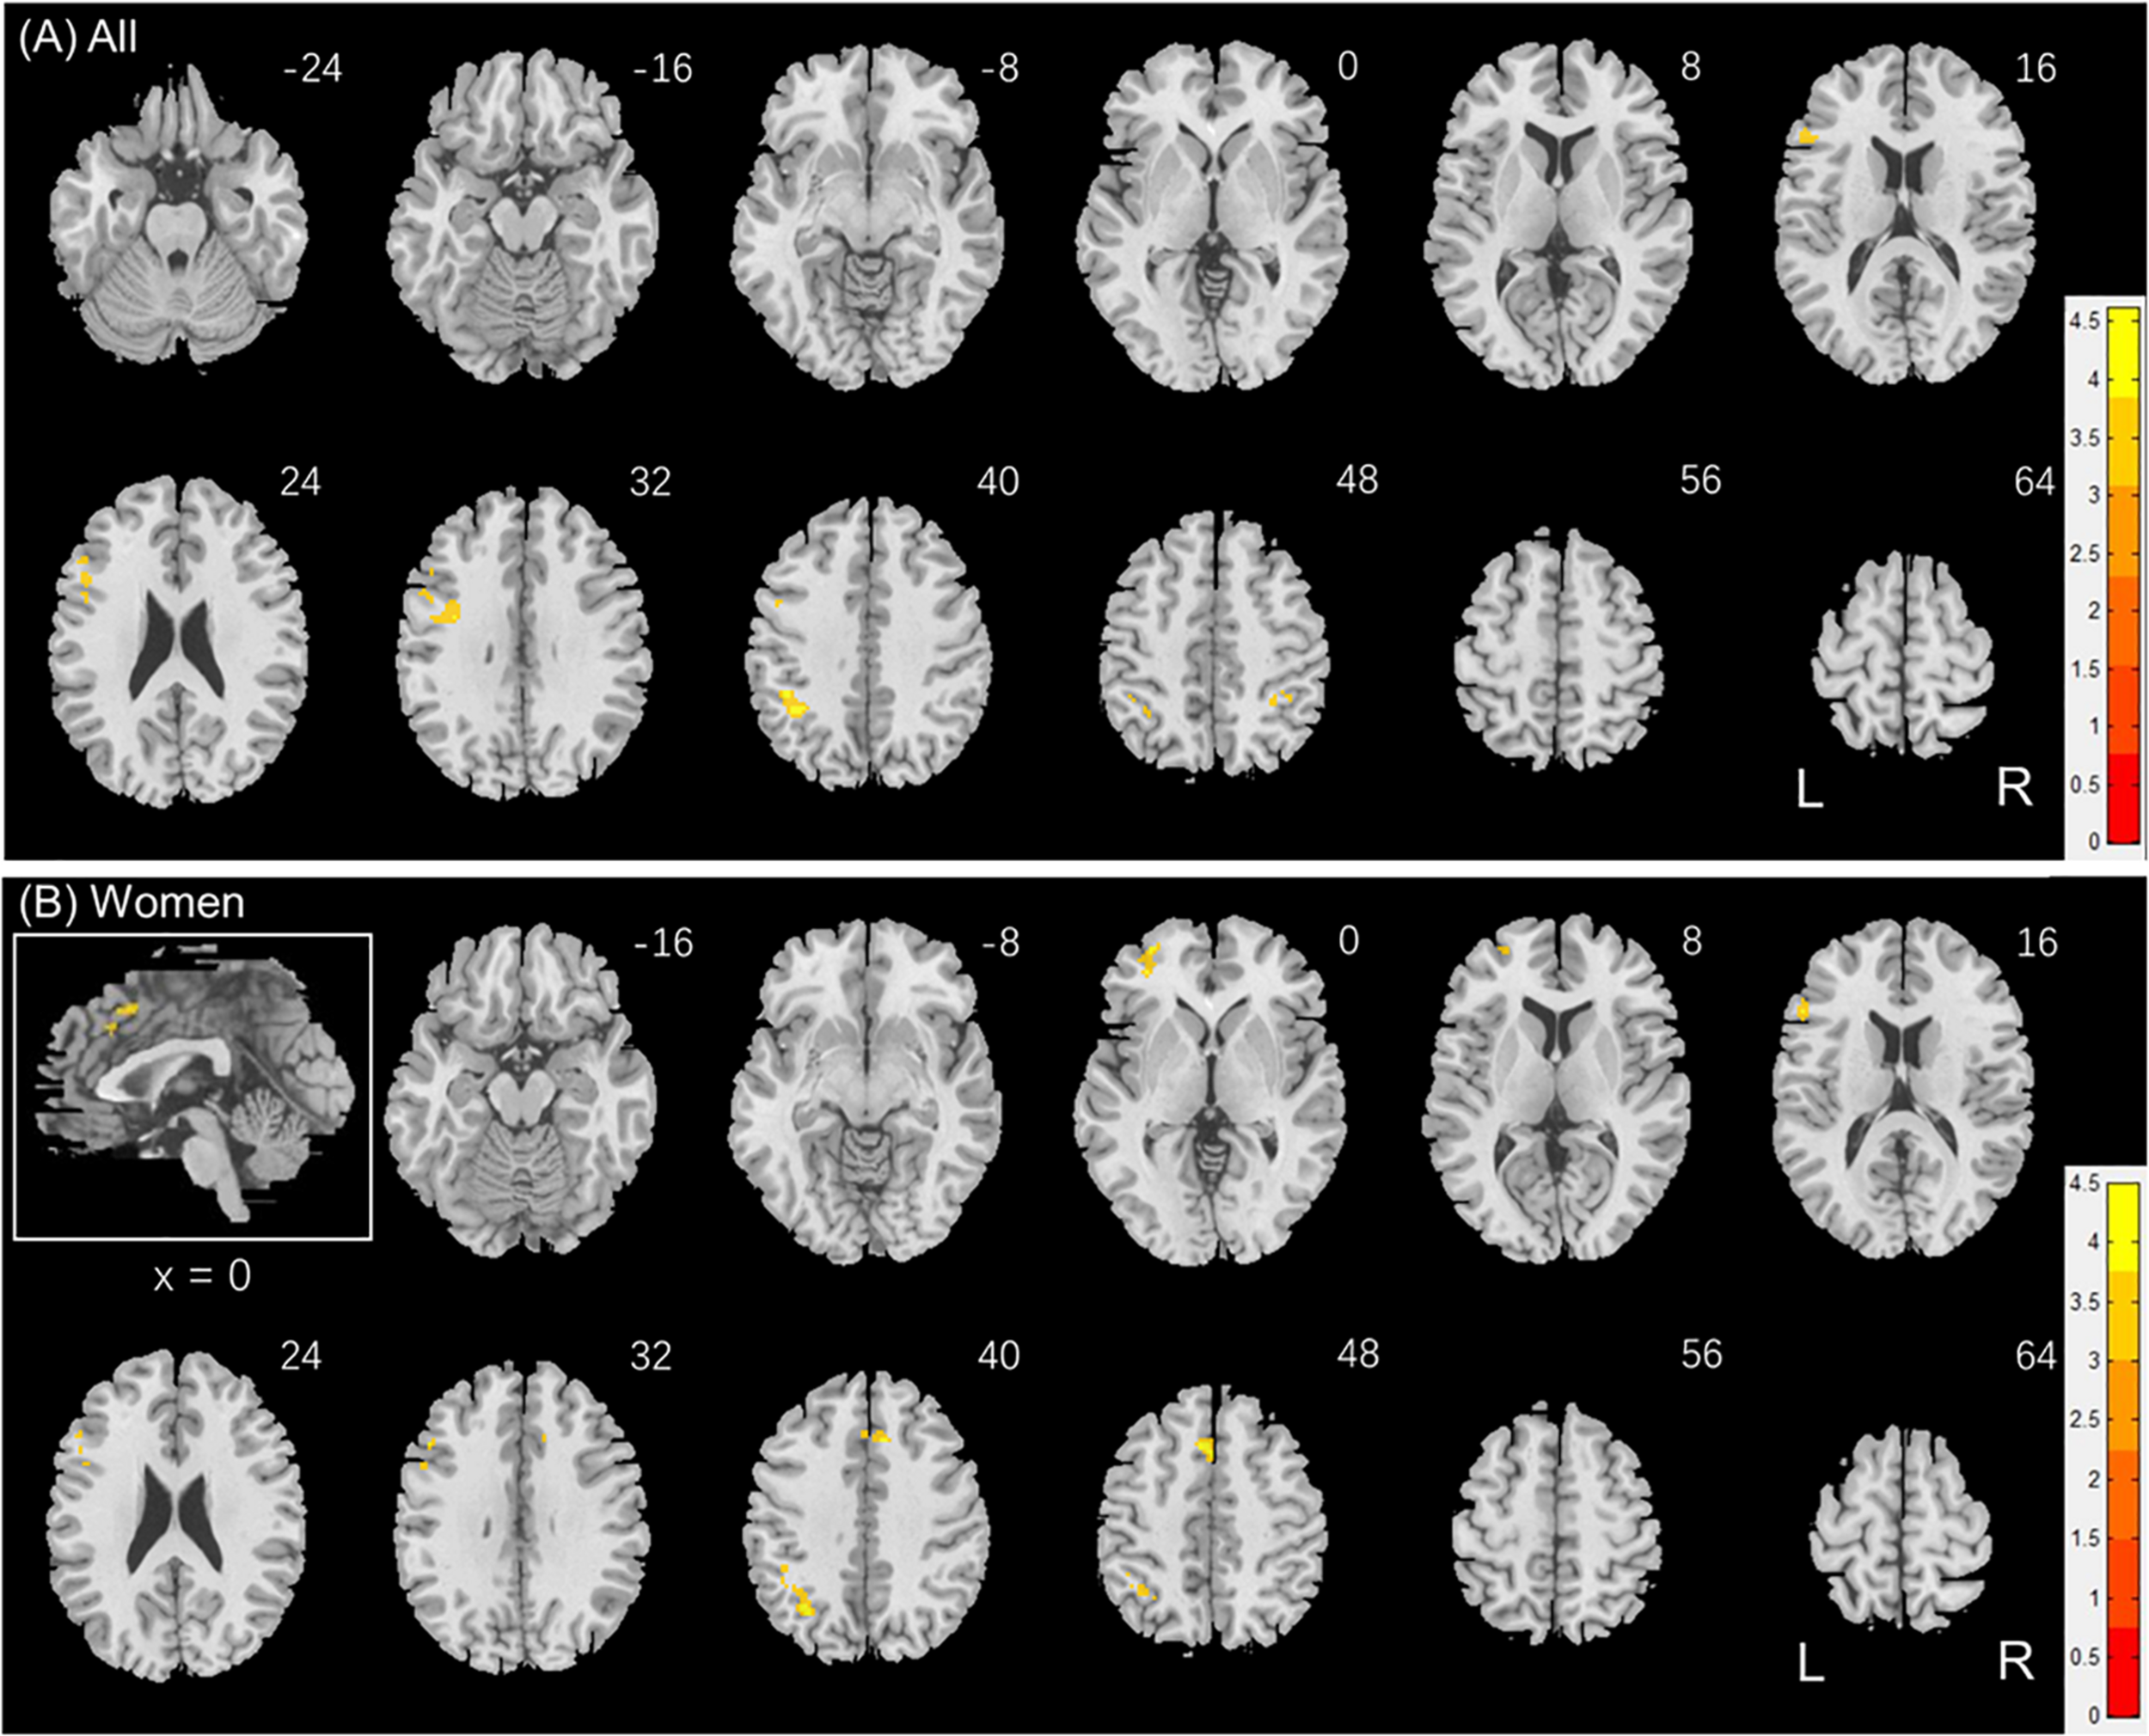

Brain Activations to Social vs. Random Stimuli in Correlation With Reaction Time

Individuals also varied in how quickly they identified social vs. random interactions. We conducted a whole brain linear regression of the contrast (social - random) against “RTSOC – RTRAN” across all subjects, with sex, age, and years of education as covariates. Clusters that met the threshold of voxel p < 0.001, uncorrected, in combination with cluster p < 0.05 FWE-corrected are shown in Figure 6A. Bilateral inferior parietal cortex, left inferior frontal cortex showed activation in positive correlation with RTSOC – RTRAN. No cluster showed activation to social vs. random in negative correlation with RTSOC – RTRAN.

FIGURE 6

www.frontiersin.org

Figure 6. Regional responses to social interaction vs. random movement in correlation with “RTSOC – RTRAN” in (A) all subjects: whole-brain regression with sex, age and years of education as covariates; and in (B) women, with age and years of education as covariates. Warm/cool color bars show clusters with positive/negative correlation with “RTSOC – RTRAN”; voxel p < 0.001, uncorrected, in combination with cluster p < 0.05 FWE-corrected. The insets highlight the clusters in a mid-sagittal section.

We next conducted a whole brain linear regression of contrast (social – random) against “RTSOC – RTRAN” for men and women separately, with age and years of education as covariates. For men alone, no clusters showed activation in positive or negative correlation with “RTSOC – RTRAN.” For women alone, left supplementary motor area, left inferior parietal cortex, left middle and inferior frontal cortex showed activation in positive correlation with “RTSOC – RTRAN” (Figure 6B).

These clusters are summarized in Table 4.